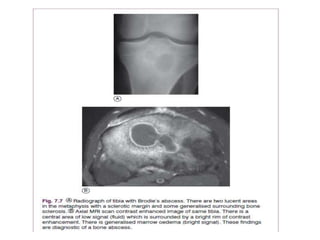

Subacute Osteomyelitis

• X-Ray we See Brodie’s Abcess:

– Small and Oval in shape

– It is surrounded by sclerotic bone

– May be mistaken for Ostieoid Osteoma

Brodie’s abscess

• This is a special form of chronic osteomyelitis which arises insidiously,

without a preceding acute attack. There is a localised abscess within the

bone, often near the site of the metaphysis. A deep ‘boring’ pain is the

• Imaging; Radiographically, the lesion is seen as a circular or oval cavity

surrounded by a zone of sclerosis ,but the site and extent of the lesion can

be shown more accurately on an MRI scan. The rest of the bone is normal.

• Results from –Less virulent Microorganism – Patient with an elevated resistance. • Occurs Mostly at the Distal Femur or Proximal Tibia • X-Ray we See Brodie’s Abcess: – Small and Oval in shape – It is surrounded by sclerotic bone – May be mistaken for Ostieoid Osteoma

• This isa special form of chronic osteomyelitis which arises insidiously, without a preceding acute attack. There is a localised abscess within the bone, often near the site of the metaphysis. A deep ‘boring’ pain is the predominant symptom. • Imaging; Radiographically, the lesion is seen as a circular or oval cavity surrounded by a zone of sclerosis ,but the site and extent of the lesion can be shown more accurately on an MRI scan. The rest of the bone is normal. • Treatment is by operation. The cavity is de-roofed and the pus evacuated. Whenever possible the cavity should be filled with a muscle flap to obliterate the dead space.